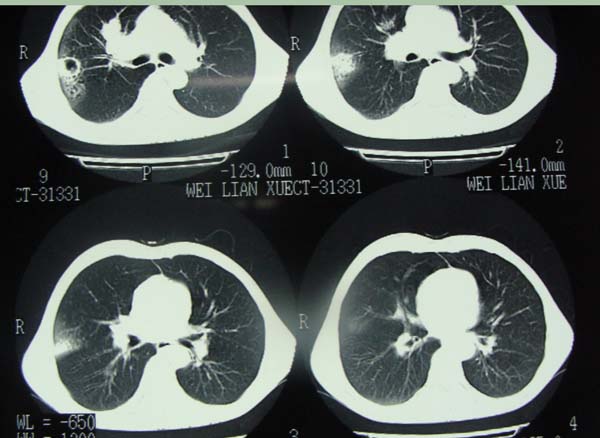

以下是引用pujunzhi在2009-6-21 21:48:00的发言:[br]右肺上叶后段见一空洞性病灶,灶周有渗出即晕征,右肺门肿大---可考虑感染性空洞和癌性空洞,先抗炎抗痨后复查并完善相关检查。有癌性空洞伴肺门淋巴结转移的可能。